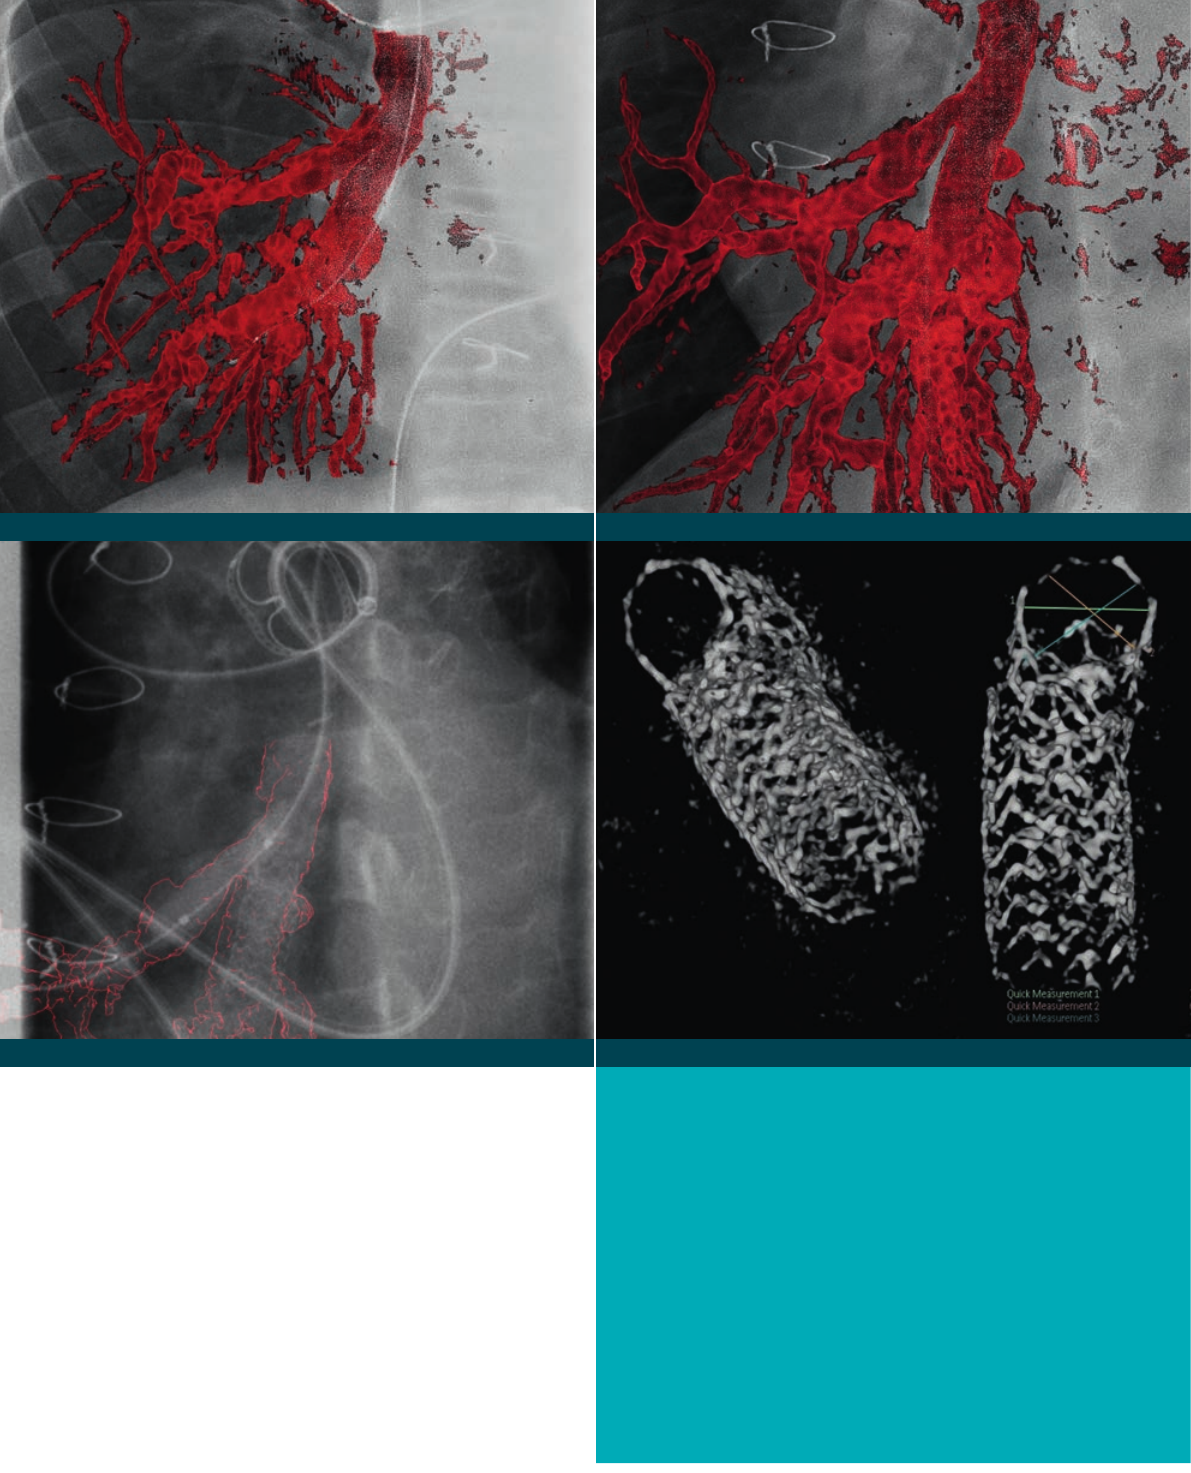

Allura Xper system AlluraClarity system

3D-RAreconstructionofthe

pulmonaryarteries.

Enhanced3Dvisualizationandnavigationtechniqueshelp

determinetheoptimalcourseoftreatmentwithgreater

precision.Thisiscriticalinpediatrics,asthevarietyin

patientanatomyandcongenitalheartdefectscanbe

signicant.Theabilitytocaptureandreuse3Ddataas

ameanstoreducetheneedforadditionalcontrastand

X-rayduringaprocedureisimportant.

Three-dimensional rotational angiography (3D-RA)

3DRAprovidesfast,high-resolution3Dimagesofthe

cardiacanatomyfromanyangulationandrotation.Ithelps

visualizecomplexvascularanomaliestofacilitatedecision

makingfortreatmentstrategies.Ratherthanmultiple2D

views,whichrequiremultiplecontrastinjections,a3DRA

providesacomplete3Doverviewoftheanatomywitha

singleinjection.The3Dimagecanbeinspectedinanyview,

eventhosethatcannotbereachedwithregular

2Dprojections.